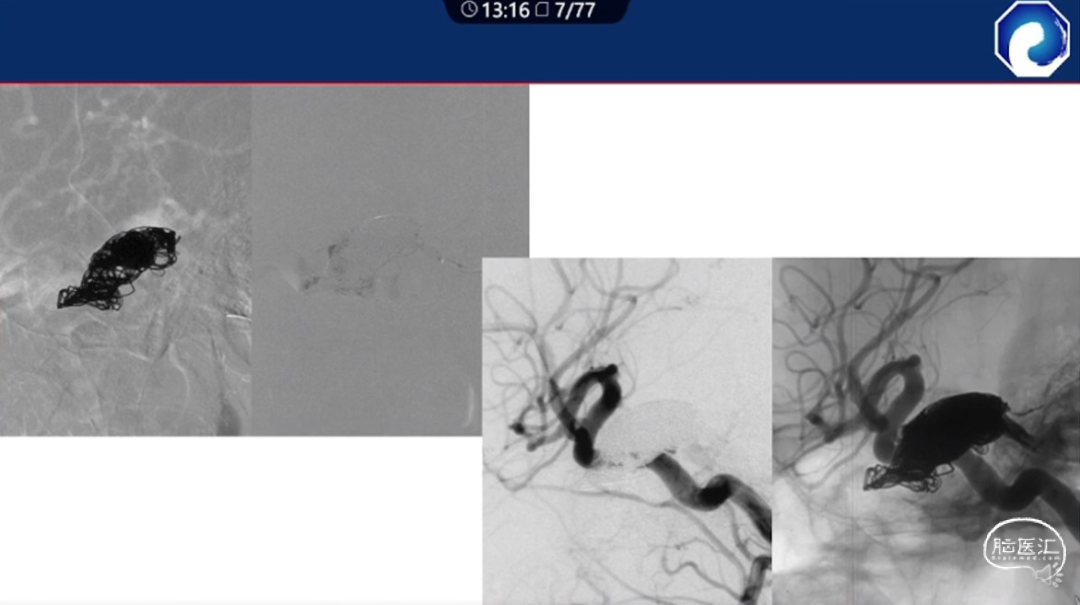

痿口静脉端精准完全闭塞是DAVF治愈的关键。

靶向性栓塞可以减少海绵窦分隔的过渡栓塞,有利于减少颅神经并发症,恢复海绵窦的正常引流功能。